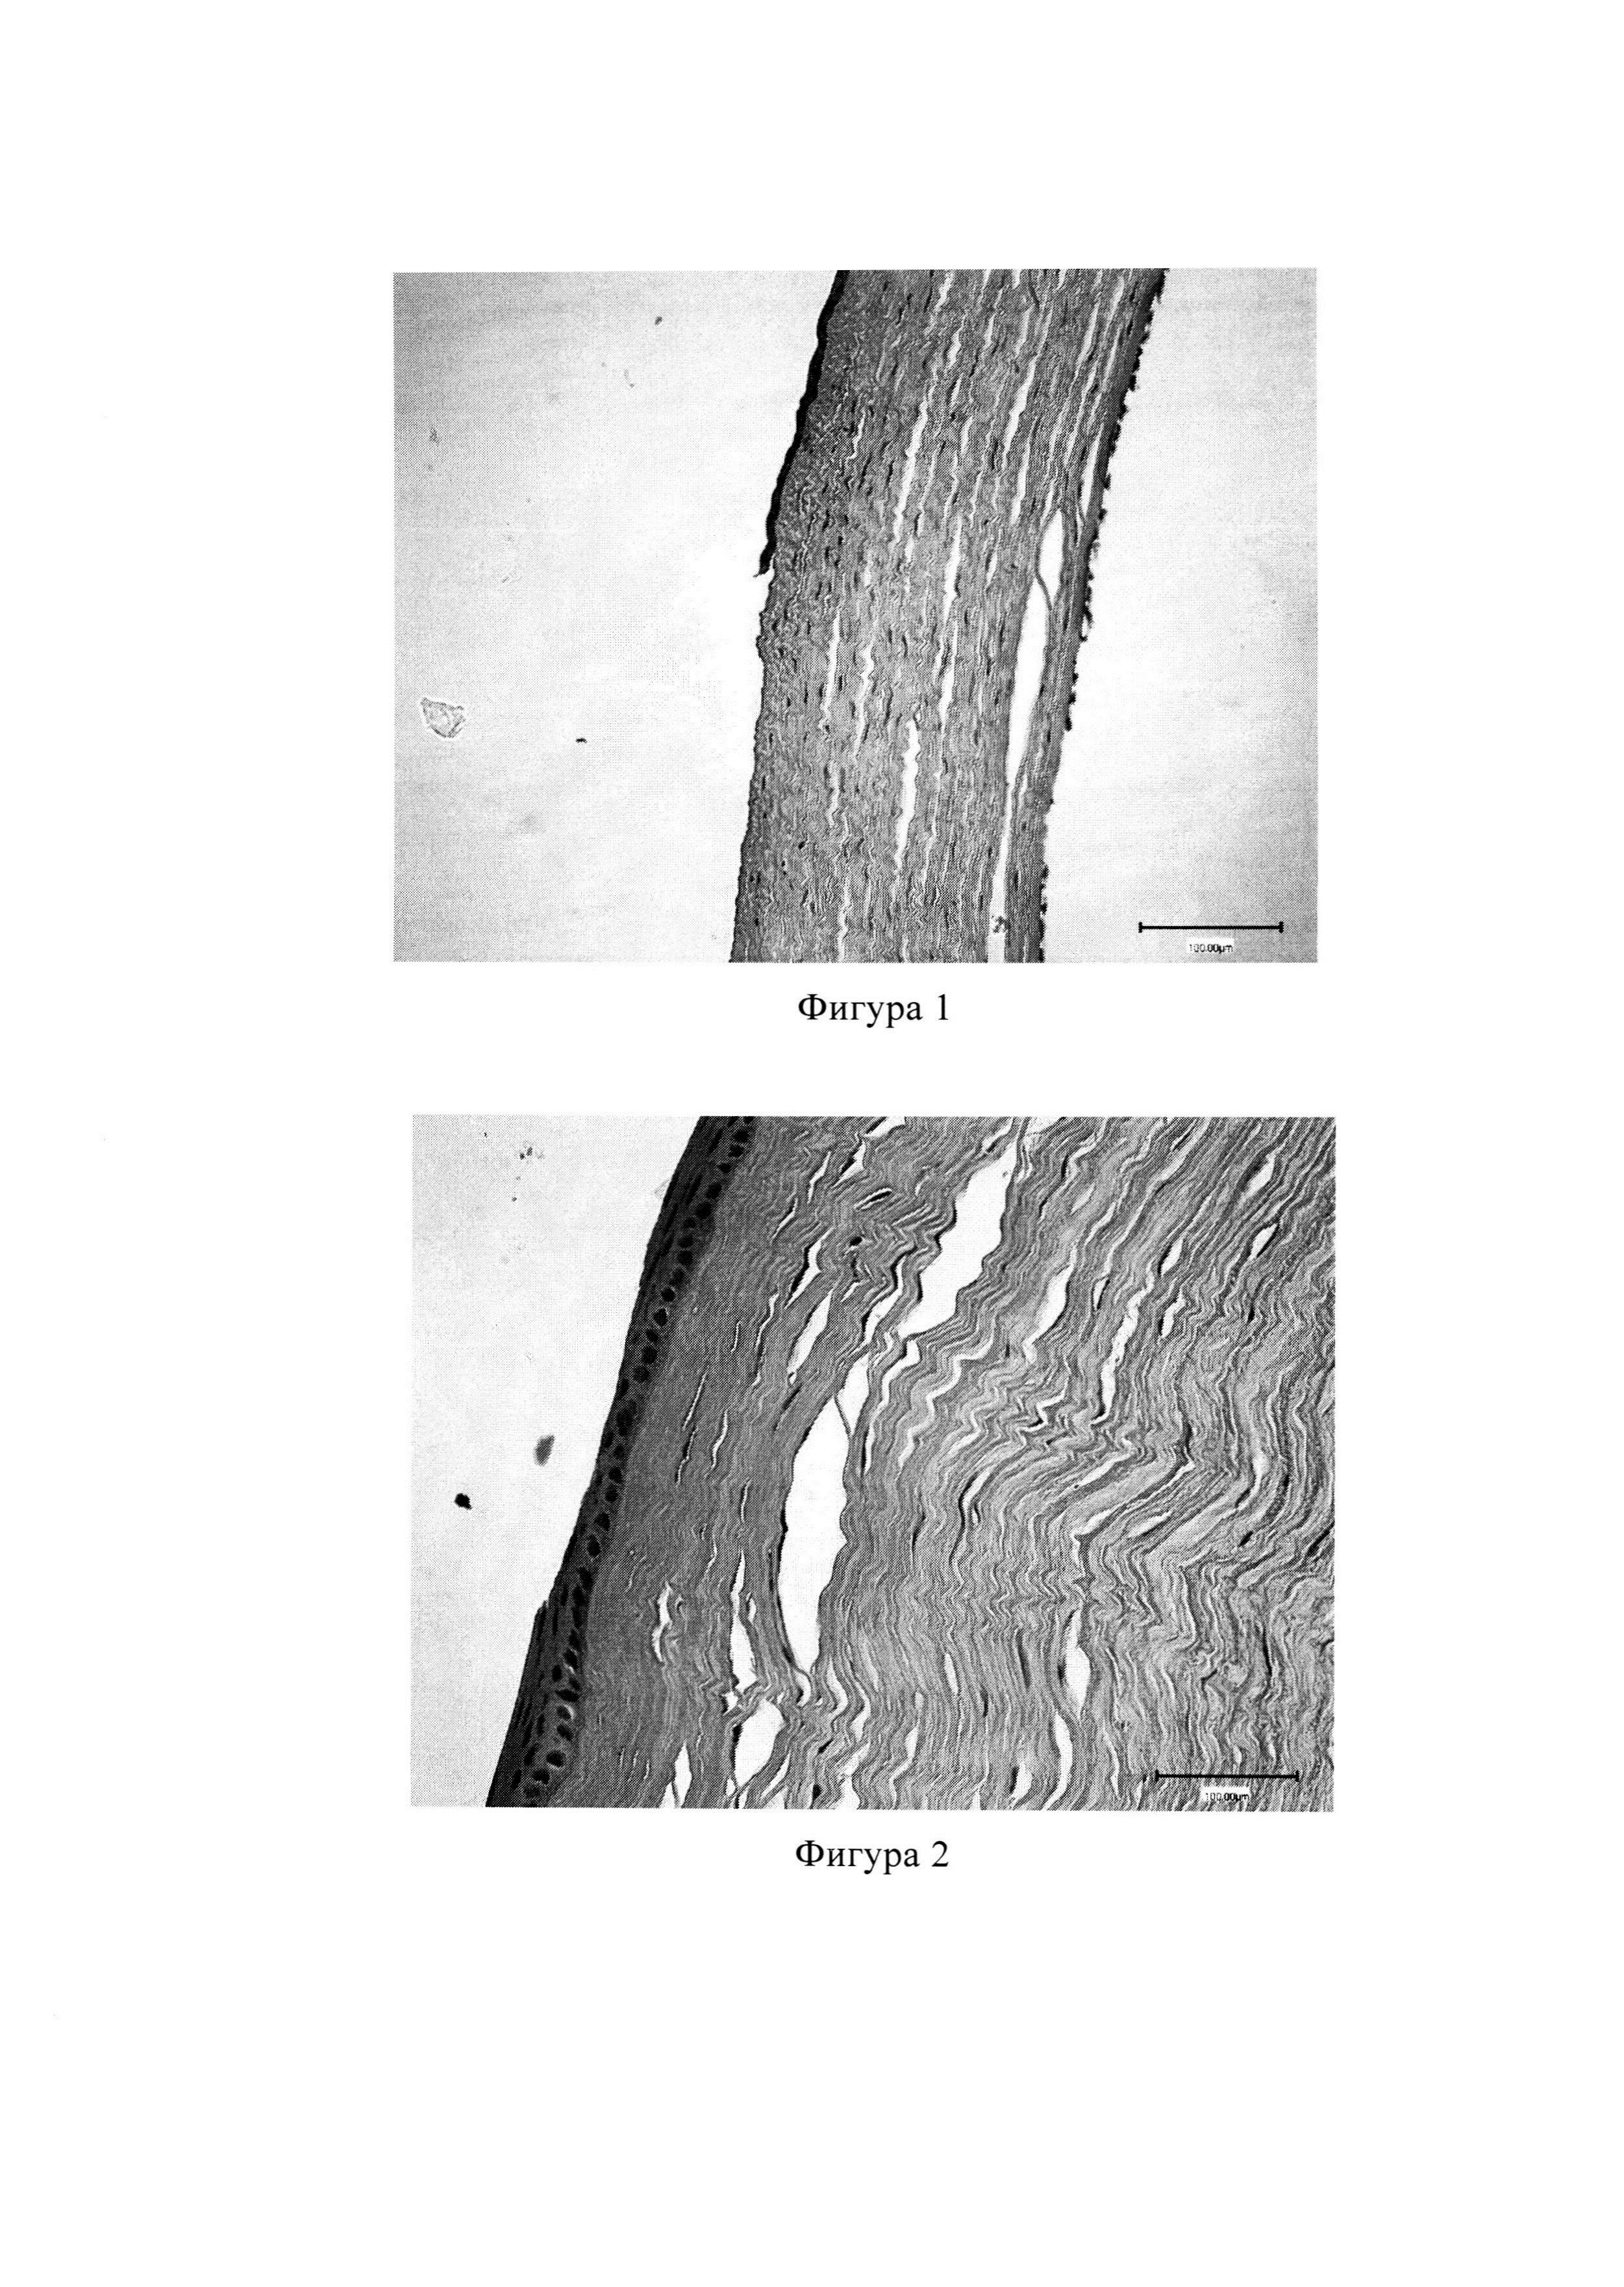

Изобретение относится к медицине, в частности к офтальмологии, и может быть использовано при лечении термического, химического поражения роговицы и конъюнктивы, послеоперационного отека роговицы после факоэмульсификации катаракты, травматических эрозий роговицы, а также для повышения регенерации роговицы. В лечении и профилактике заболеваний глаз используют различные методы введения лекарственных веществ в ткани глаза. Наиболее широкое применение нашли глазные капли, мази, гели, подконъюнктивальные, парабульбарные и внутрикамерные инъекции. Инсталляционная методика имеет ряд недостатков, такие как частые закапывания в зависимости от выраженности заболевания, закапывание антибиотиков не сопровождается достижением во влаге передней камеры глаза необходимой концентрации для подавления роста микроорганизмов [Барри П., Руководство ESCRS по профилактике и лечению эндофтальмита после операции по удалению катаракты: данные, дилеммы и выводы / П. Барри, Кордовес Л., Гарднер С.; пер. с анг. Б.Э. Малюгина. Temple house, Ирландия 2013. - 30 с.]. Эффективность лечения часто зависит от состава лекарства, а также от лекарственной формы. При повреждении структуры роговицы декспантенол активирует митоз эпителиальных клеток и ускоряет их миграцию в зону раневого дефекта. Кроме того, декспантенол предотвращает образование рубцов стромы роговицы, влияя на формирование нормальной структуры фибробластов и активизируя их пролиферацию. При использовании декспантенола в регенерированных участках происходит восстановление правильной многослойной структуры коллагеновых волокон, что положительно сказывается на восстановлении прозрачности роговицы [Ventura А.С., Walti R., Bohnke M. Corneal thickness and endothelial density before and after cataract surgery // Br. J. Ophthalmol. 2001. Vol. 85. №1. P. 18-20]. Пленки - твердая дозированная лекарственная форма, представляющая собой одно или многослойные тонкие пластинки подходящего для применения размера, содержащие одно или несколько действующих веществ и вспомогательные, в том числе пленкообразующие, вещества. Пленки как лекарственная форма впервые появились в 1970 году в офтальмологии. Глазные лекарственные пленки (ГЛП) имеют пролонгированное действие, что позволяет поддерживать необходимую концентрацию лекарства в лечебной зоне длительное время, применяются один раз в сутки, их применение исключает частые лечебные процедуры, тем самым освобождая медицинский персонал. Вследствие постепенного выделения действующего вещества ГЛП легко переносятся пациентами, имеют минимальные побочные и токсичные действия [Майчук Ю.Ф. Глазные лекарственные пленки / Ю.Ф Майчук, В.И. Поздняков, Г.Л. Хромов, Е.Б. Конева, Л.Н. Старукова // Вестник офтальмологии. - 1974. - №6. - стр. 419-423]. Заболевания роговицы и травматические повреждения, как одни из важных причин снижения зрения, - представляют собой актуальную проблему в офтальмологии и ставят задачу поиска новых форм лекарственных средств для лечения патологий органа зрения [Waring G.O. 3rd, Bourne W.M., Edelhauser H.F. et al. The corneal endothelium. Normal and pathologic structure and function // Ophthalmology. 1982. Vol.89. №6. P. 531-590.]. Известна глазная лекарственная пленка, содержащая следующее соотношение компонентов, мас. %: поливиниловый спирт 82,5, арабиногалактан - 16,5 и левофлоксацин - 1 [патент RU 2404779, 2010 г.]. Известна глазная пленка, содержащая поливиниловый спирт, дигидрокверцетин в качестве активного вещества растительного происхождения, моксифлоксацин в качестве антибиотика. Глазные лекарственные пленки с моксифлоксацином удобны в применении, обладают продолжительным антимикробным, антиоксидантным, иммуномодулирующим, противовоспалительным свойствами [патент RU 2581025, 2016 г.]. Наиболее близким аналогом изобретения является глазная пленка, которая содержит измельченную нативную роговицу глаз крупного рогатого скота 0,25 г, поливиниловый спирт 99,25 г, гамма-глобулин 0,25 г, гентамицин 0,25 г. Глазная пленка может быть использована при лечении травматических ожоговых и дистрофических повреждений роговой оболочки и конъюнктивы [патент RU 2173178, 2001 г.]. Недостатками данной пленки являются сложность химического состава и трудоемкий затратный технологический процесс ее получения, кроме этого, эффективность данной пленки не проверена при химических ожогах роговицы. Задачей предлагаемого изобретения является расширение арсенала лекарственных средств для лечения патологий роговицы. Технический результат при использовании изобретения - повышение регенерации роговичной ткани Заявляемая ГЛП содержит в качестве пленкообразующей основы поливиниловый спирт, а в качестве биологически активного вещества содержит метилурацил при следующем содержании компонентов, в г на 100,0 мл очищенной воды: поливиниловый спирт - 3,3 метилурацил - 0,12. Метилурацил (2,4-диоксо-6-метил-1,2,3,4-тетрагидропиримидин) - это препарат, улучшающий трофику, усиливающий рост и размножение клеток, стимулирует процесс регенерации в поврежденных тканях, обладает противовоспалительным действием, ускоряет заживление ран, ожогов, повышает сопротивляемость организма к инфекциям. Изобретение иллюстрируется фигурами 1-5, на которых представлены гистологические препараты глаз экспериментальных кроликов №№1-4, которые окрашены гематоксилин-эозином и исследованы методом световой микроскопии. Предлагаемую глазную пленку получают следующим образом. На первом этапе технологии приготовления ГЛП подготавливали помещения и вспомогательные вещества, получали в асептических условиях водный раствор метилурацила. Глазные лекарственные пленки с метилурацилом получали следующим образом: в асептических условиях в герметично закрывающуюся емкость помещали поливиниловый спирт и заливали заранее приготовленным водным раствором метилурацила. Оставляли при комнатной температуре в течение 12 часов для полного набухания поливинилового спирта. Затем раствор полимера термостатировали при температуре 80-90°С до его полного растворения. Полученный раствор фильтровали через стерилизующий фильтр и разливали в простерилизованные формы с ячейками стерильной пипеткой. Подложку с ячейками помещали в термостат и высушивали в температуре 45°С до остаточной влажности 5%. Полученные пленки вынимали из ячеек и помещали в стерильные флаконы по 10 мл и герметично укупоривали под обкатку. Известно, что метилурацил стимулирует защитную активность фагоцитов [патент РФ 2485118] и обладает антиоксидантным эффектом, противомикробной активностью [Мещерякова С.А., Катаев В.А., Фаттахова И.Я. и др.). Синтез и противомикробная активность ацетанилидов и ацетилгидразонов тиетанилпиримидин-2,4(1H,3H)-дионового ряда // Химико-фармацевтический журнал, 2015. - Т. 49. №9. - С .28-31]. Для экспериментальной проверки заявляемого средства были приготовлены образцы пленок, с использованием следующих пленкообразователей: поливиниловый спирт (ПВС), поливинилпирролидон (ПВП), метилцеллюлоза (МЦ), натрий карбоксиметилцеллюлоза (Na-КМЦ), желатин. В качестве пластификатора во все составы, кроме состава с ПВС, вводили глицерин (таблица 1). Полимеры заливаются водой (может быть нагревание, в зависимости от свойств полимера). Масса тщательно перемешивается ручной или механической мешалкой. Смесь выдерживается при комнатной температуре и периодическом перемешивании до полного растворения полимера, затем добавляется глицерин, проводится дополнительное смешивание. Критериями для отбора наиболее подходящего состава пленок служили следующие показатели качества: органолептические свойства, рН водного раствора, толщина, влажность, время растворения. Результаты исследования показателей качества пленок различного состава представлены в таблице 2. Все растворы пленок имеют нейтральную реакцию. На основании анализа всех показателей выбрали пленки состава №1 с пленкообразователем ПВС. У данного состава по сравнению с другими составами оптимальные органолептические показатели, влажность, толщина и время растворения (пролонгирование). Готовая лекарственная пленка бесцветная, прозрачная, обладает высокой эластичностью и хорошей адгезией. ГЛП удобна в применении, хорошо совместима с глазной жидкостью, что способствует постепенному высвобождению действующего вещества, обеспечивая пролонгированное действие. Пленку рекомендуется хранить защищенном от света месте, при температуре от 8 до 15°С. Предлагаемая ГЛП закладывается в конъюнктивальную полость 1 раз в день в течение 7-21 дней. Применение ГЛП улучшает функциональные исходы, сокращает сроки лечения, пленка хорошо переносится, экономична и удобна в использовании. Показателем клинического выздоровления считается восстановление эпителиально-стромального пласта роговицы. Предлагаемая ГЛП апробирована на переносимость тканями глаза в эксперименте на 5 кроликах породы шиншилла. Экспериментально вызвали химический ожог роговицы (по методу Обенбергера) аппликацией диска фильтровальной бумаги диаметром 8 мм, смоченной 3% уксусной кислотой, экспозицией 5 секунд. Затем промывали конъюнктивальную полость 0,9% физиологическим раствором в течение 10 минут. После этого в левые глаза кроликов №№1, 2, 3, 4 (4 глаза) закладывали ГЛП с метилурацилом 1 раз в день весь период эксперимента. В левый глаз кролика №5 закладывали гель декспантенола 5% (корнерегель) 2 раза в день, а правый глаз оставляли без лечения для наблюдения в условиях отсутствии лечения. Для профилактики бактериальной инфекции всем кроликам закапывали глазные капли тобрамицин 0,3% 4 раза в день. Терапевтическую эффективность лечения оценивали по следующим признакам: рассасывания отека роговицы, уменьшения светобоязни, инъекции, раздражения и отека конъюнктивы, уменьшения сроков лечения. Гистологическая картина роговицы кролика на вторые сутки наблюдения: в центральной зоне роговицы выявлялась тотальная десквамация эпителия от основного вещества роговицы, повреждение Боуменова мембраны. Эпителиоциты на периферии роговицы определялись как клетки с гиперхромными уплощенными ядрами и располагались в один ряд. Строма отечная, воспалительно-клеточная инфильтрация отсутствовала (фиг. 1). На 7-е сутки наблюдения после кислотного ожога очагов эрозии не выявлены и наблюдается тотальная эпителизация роговицы. Передний эпителий характеризовался неравномерностью и неоднородностью толщины пласта. Наряду с однорядным камбиальным эпителием призматической формы обнаруживались пласты уплощенных эпителиоцитов, вектор которых был направлен вдоль длинной оси поверхности роговицы. Направление миграции было от периферии (от лимба) к центру, т.е. центростремительно (фиг. 2). Это свидетельствует о миграции эпителиоцитов со стороны лимба для замещения утраченного переднего эпителия. В центральной зоне спустя 14 суток определялся многослойный плоский неороговевающий эпителий в виде 5-6 клеточных слоев, визуализируется центростремительная эпителизация дефекта роговицы (фиг. 3). В этом же сроке наблюдения в перилимбальной зоне определялись слои эпителиальных клеток с миелиновыми гранулами, что свидетельствует о нормальном процессе эпителизации роговицы (фиг. 4). На гистологической картине на 21-е сутки исследования наблюдалось 6-7 слоев эпителия, восстановление многослойного плоского неороговевающего эпителия в центральной зоне роговицы (фиг. 5). В контрольном левом глазу 5-го кролика тоже наблюдались вышеперечисленные изменения, за исключением некоторых участков, где наблюдалось относительно запоздалое закрытие дефекта, что подтверждается данными экспериментальных работ других авторов [Пронкин И.А. Разработка метода терапии рецидивирующих эпителиальных дефектов роговицы на основе «Протектора эпителия роговицы гелевого»: дис. … канд. мед. наук. - Москва, 2017. - 119 с.]. На глазу с моделью ожога без лечения дефект эпителия сохранялся на 21-е сутки наблюдения.